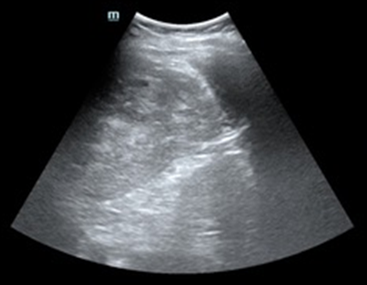

Tras varias horas en observación el paciente comienza con tendencia a la hipotensión. Permanece en observación y monitorización persistiendo hipotensión arterial con buena ventilación bilateral en la auscultación pulmonar. En la exploración abdominal presenta dolor y defensa a la palpación profunda en hipocondrio izquierdo. Se realiza Ecografía clínica a pie de cama del paciente descartando hemoneumotótax y derrame pericárdico; al explorar el abdomen se objetiva líquido libre en espacio de Morrison y eje espleno renal, con imagen compatible con rotura del parénquima esplénico. Gasométricamente se objetiva anemización con caída de cifras de Hb de 15,7 g/dl en análisis inicial a 13,8 g/dl. Se solicitan pruebas cruzadas, se reservan hemoderivados y se contacta con cirugía para traslado del paciente a quirófano.